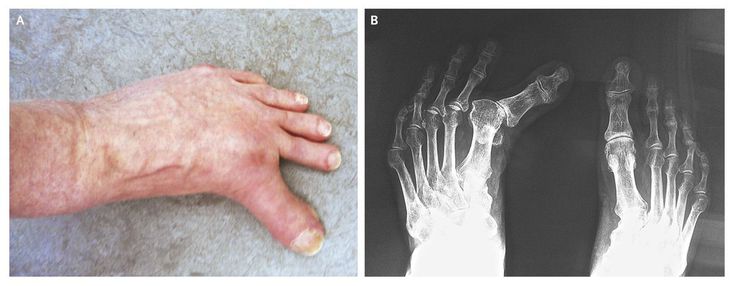

An otherwise healthy 73-year-old man presented with painless hallux varus (Panel A), a deformity of his left great toe that had been progressing over many years. He reported having a fasciectomy of the right hand for Dupuytren's contracture, which recurred postoperatively. He now had Dupuytren's contractures of both hands There was no relevant family history, and he was not taking any medication. Physical examination confirmed the left hallux varus, for which he required a custom-made shoe, and revealed thickening of the plantar fascia on the medial aspect of the left foot. A preoperative radiograph showed clinically significant deformity of the left first metatarsal (Panel B). During surgery , he underwent fusion of the first metatarsophalangeal joint for correction of the hallux varus, osteotomy of the fifth metatarsal for a bunionette, or tailor's bunion and release of the plantar aponeurosis. Histologic evaluation of the fascia showed fibromatosis characteristic of Ledderhose's disease, a rare, idiopathic proliferative disorder of the plantar aponeurosis, which may be associated with Dupuytren's contractures. At follow-up 6 months after surgery, the patient was doing well.